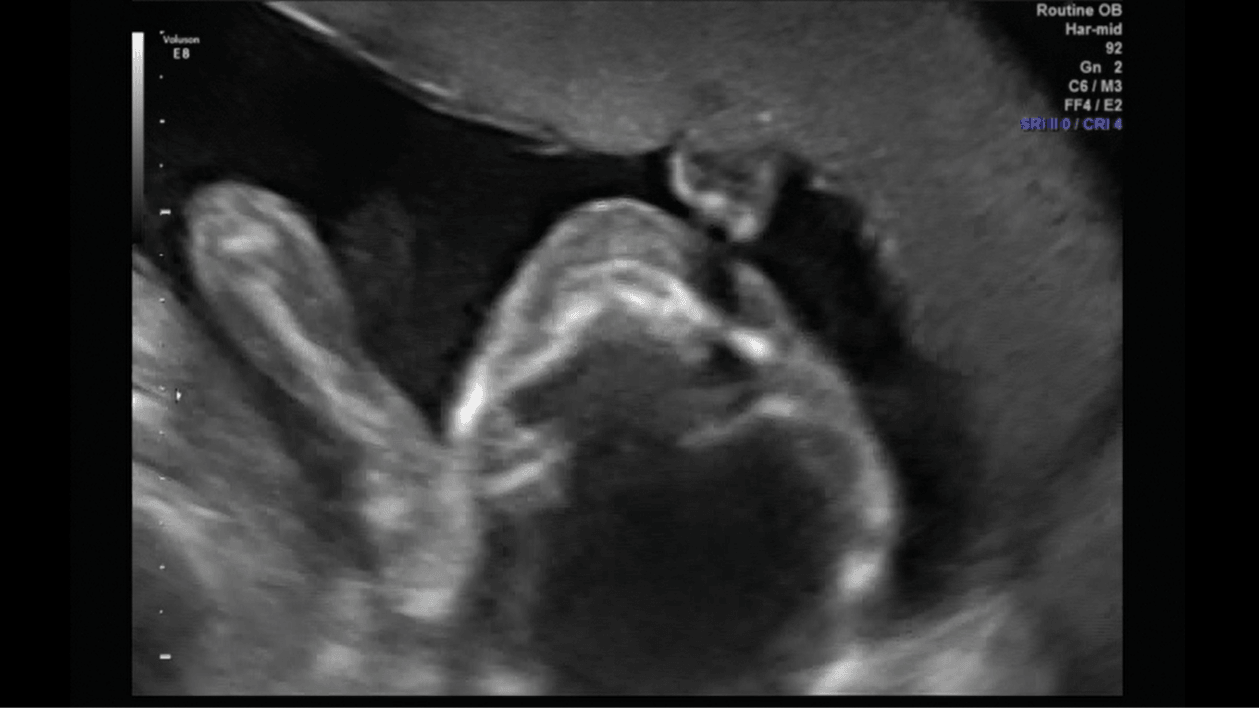

Porobiłam trochę screanów z usg połówkowego, więc pomyślałam, że wrzucę, mam nadzieję, że nie maci mi za złe ilości :D

Rączka przy główce :)

3.png